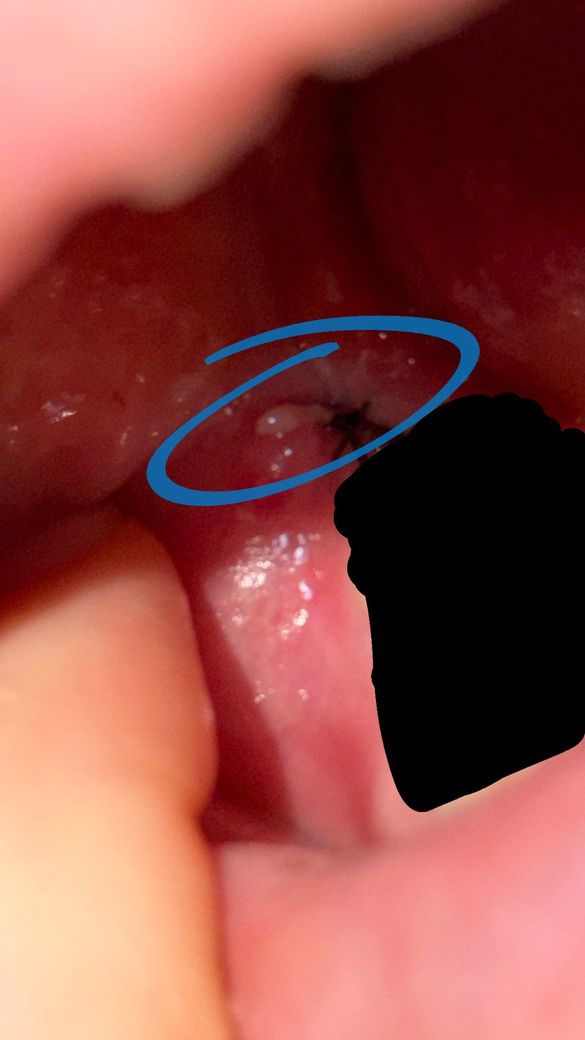

매복사랑니 발치 후 염증인지 궁금합니다

2월 28일에 매복 사랑니 발치를 했는데요

오늘 보니까 저렇게 염증처럼 뭐가 생겨있어서요..

염증일까요 아님 뭘까요 ㅜㅜ 내일이라도 치과 가봐야 할까요

• 1번 째 사진

갑자기 통증이나 불편감이 커지지 않는다면 정상적인 회복 과정입니다. 아직까지 일주일도 되지 않았으므로 잇몸 자체가 약간 부어 있을 수 있습니다. 드라이소켓 처럼 갑자기 통증이 나타나는 것이 아니라면 대부분 사람마다 편차가 있을 뿐 정상적으로 회복되니 걱정하지 않으셔도 됩니다.

염증이 생긴것은 맞으나 발치 부위에서 흔하게 있을 수 있는 일입니다 처방받은 항생제와 진통제와 도움이 될 겁니다